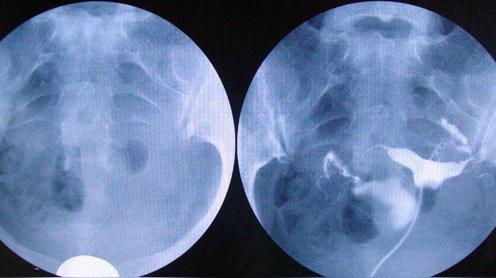

做子宫造影有哪些注意事项

做输卵管造影要多少钱?专家解读造影费用

做造影对身体的危害有哪些呢什么是子宫输卵管造影

但都没有怀孕.第三个月自己决定做造影.

什么情况下需要做输卵管造影

什么情况需要做输卵管造影

跟大家分享一下我的输卵管造影经历

哪些人需要做输卵管造影?

姐妹们没有怀上,一定做个造影看看输卵管是否畅通.

4步讲解输卵管造影检查过程

输卵管造影不要随便做输卵管造影注意事项

输卵管造影2月19日做的造影2月20

备孕检查做输卵管造影疼吗影响输卵管造影疼痛的因素

你好,我做造影检查左侧输卵管梗阴,右侧

不孕,做了造影疑似宫腔粘连了帮忙看下

输卵管造影很疼吗?是怎么做的?

做输卵管造影前后,该需要注意什么?

做个输卵管造影能检查还能治疗?它有什么神奇之处?

输卵管造影检查注意事项

做输卵造影要做什么检查

超生输卵管造影费用图片合集